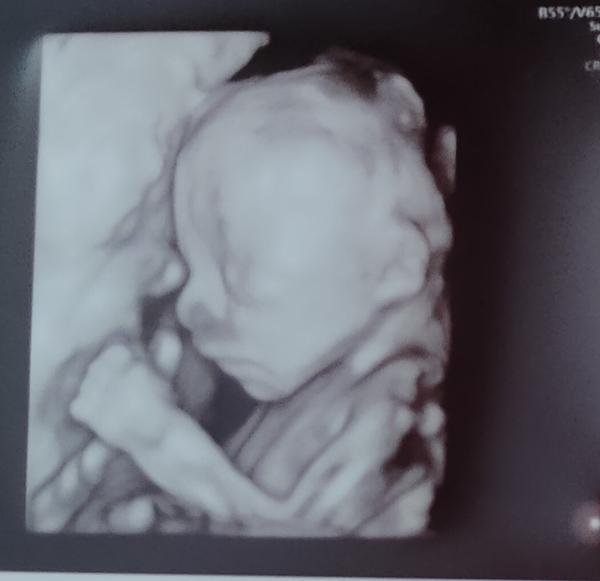

Ahooj, tak se po delší odmlce ozývám 😁 Nejak nebyl čas ani nálada,ja nevím ty hormony to je katastrofa 🥺 jsem buď vzteklá jak pes nebo se mi chce brečet, všechno a všichni mi vadí 🤣 Nemůžu jíst žádné maso,ryby ani šunky,max občas zakamuflovane kuřecí, takže jídlo je jedno velké peklo🤣 Minulý tyden jsme měli 2.screening, naštěstí je vse ok☺️ Dozvěděli jsme se i pohlaví,ale tak, že nám ho doktor napsal na papirek a s papirkem jsme jeli pro balonek, který naplní barevnýma konfetama, ten jsme pak doma praskli a natočili to na video abychom to pak poslali ostatním 😁 schválně, má někdo tip?

Tak já si tedy podle te fotky myslím, že to bude kluk 🥳💙